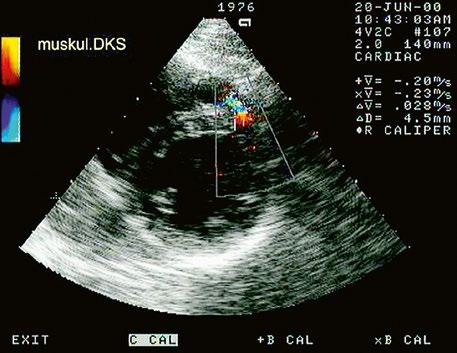

z muskulární – tvoří asi 5–20 % VSD, je ze všech stran ohraničen muskulárním septem (Obr. 45.26 , Obr. 45.27, Video 45.25, Video 45.26);

Obr. 45.27 TTE, parasternální projekce na krátkou osu na úrovni papilárních svalů, barevná dopplerovská echokardiografie ukazuje malý muskulární marginální defekt komorového septa s levopravým zkratem.